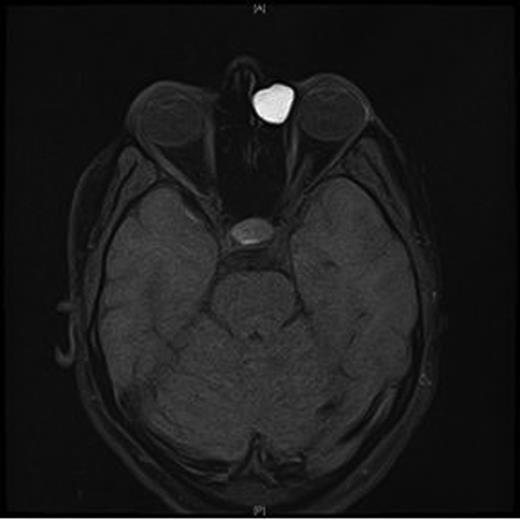

An MRI scan of the orbits showed a well-defined, thin-walled 22 × 16 mm cyst medial to the left orbit containing fatty/proteinaceous material, which was lying within and mildly expanding the left ethmoid air cells (Figs 1–3).

A CT scan of the paranasal sinuses and orbits revealed the cystic expansile 1.6 cm mass at the left medial canthus to be of soft tissue density. The lateral wall of the mass expanded outwards into the orbit (suggesting an anterior ethmoidal mucocele) rather than being pushed medially (which could have been indicative of a dacryocystocele) (Fig. 4).